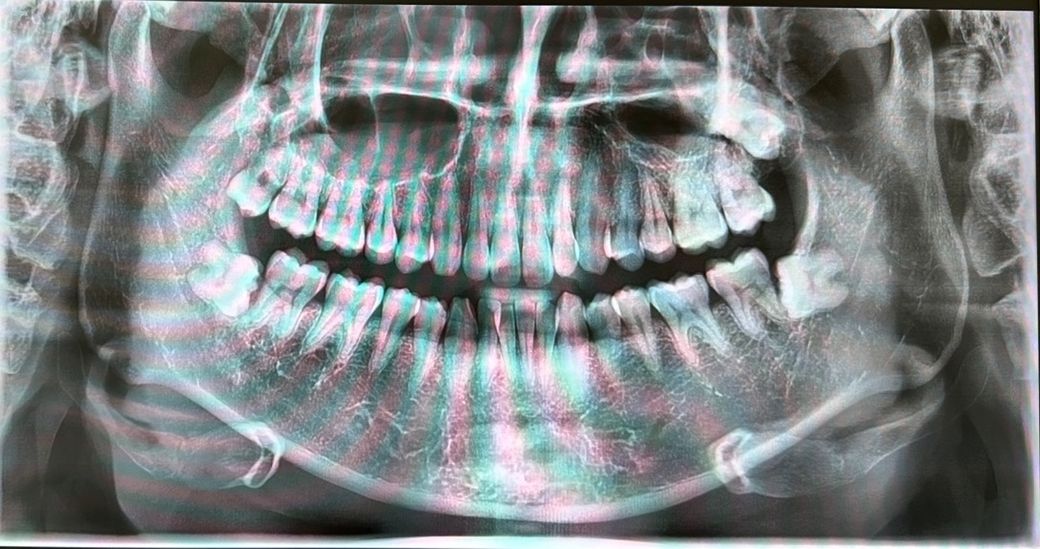

교정을 할 때 사랑니를 미리 발치하는 편이 낫나요? 아니면 그냥 두는 편이 나을까요?

사랑니를 안 뽑고 살아도 지장은 없을까요? 3개는 전부 잇몸 안쪽에 있는 거 같은데 문제가 없을지..

그리고 위쪽의 오른쪽 사랑니 때문에 주기적으로 붓는 건 그냥 둬도 괜찮을지 모르겠어요.

교정을 시작했다면 사랑니는 발치하는 것이 좋습니다. 사랑니를 안 뽑아도 지금은 문제가 되지 않겠지만 추후 문제를 일으킬 가능성이 매우 큽니다. 또한 이미 위쪽 오른쪽 사랑니는 주기적으로 붓는다는 것은 관리가 되지 않으므로 발치하는 것이 맞습니다.

사진상으로 보면 치열등에 크게 문제가 잇어 보이진 않습니다. 교정은 환자분의 선택하시면될것같고, 사랑니 발치 여부도 교정진단을 먼저 받아보시는게 좋을것같습니다.

인접치의 손상, 지치주위염, 치아우식증, 치아낭종 등의 소지가 있는 사랑니는 먼저 발치를 하는 것이 좋습니다..교정은 가능할수 있으나 선택사항입니다.